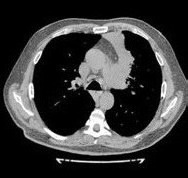

От предложенной по месту жительства эксплоративной операции (торакотомия) пациент отказался и самостоятельно обратился в консультативно-поликлиническое отделение (КПО) ФБГНУ «ЦНИИТ» для уточнения диагноза. При обследовании в КПО реакция на пробу Манту с 2ТЕ ППД-Л через 72 ч – отрицательная, реакция на пробу с АТР (антиген туберкулезный рекомбинантный) через 72 ч – отрицательная. Клинический анализ крови и мочи – без особенностей. По данным КТ ОГК от 22.08.2017 г., у пациента выявлены сочетанная аденопатия средостения, преимущественно с поражением групп лимфоузлов 2R, 4R, 7, 4L, а также дистелектаз S1-2 и S3 левого легкого, связанный с аденопатией (рис. 1)2

Рис. 1. Аксиальные срезы компьютерной томограммы в легочном (а) и средостенном (б) режимах пациента А.